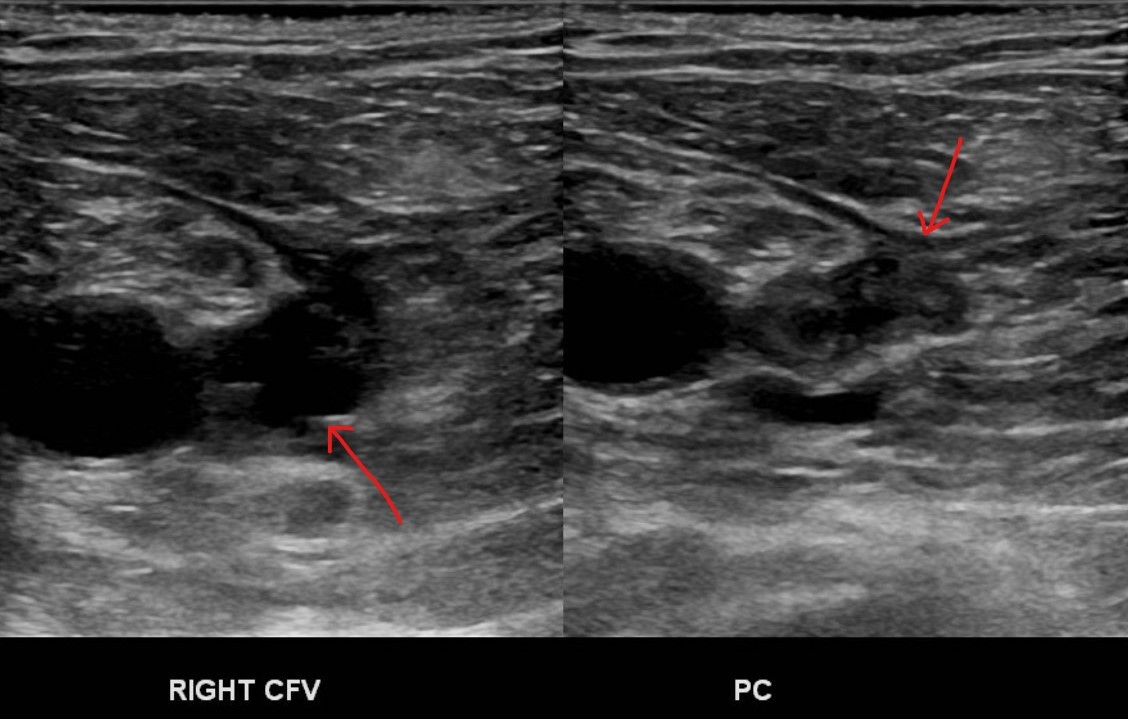

Here is an example of a mobile thrombus. You can see what I mean. It is not very stable at this point: